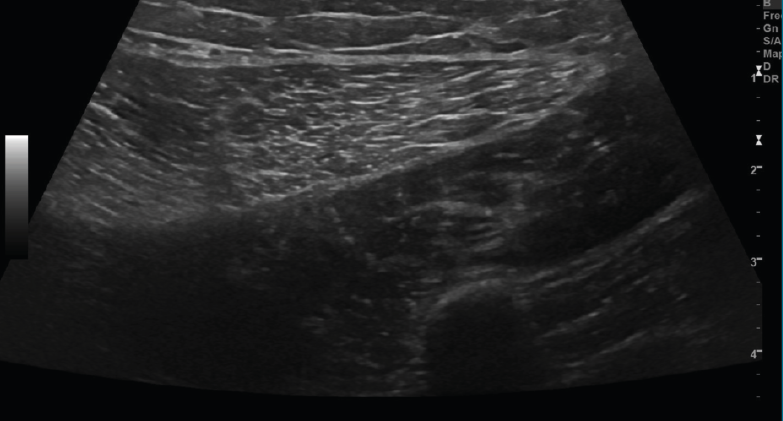

Se describen 4 grados de lesión muscular: grado 0, con ecografía negativa a pesar de tener clínica sugestiva; grado 1, con hiperecogenicidad en la lesión; y los grados 2 y 3, con regiones hipoecoicas por líquido adyacente a las fibras musculares. Cuando hay cicatrización, desaparece la región hipoecoica(8)(Figuras 11, 12, 13 y 14).

Figura 14. Corte transversal de una ecografía de pierna: imagen de cicatrización de una rotura musculoaponeurótica.